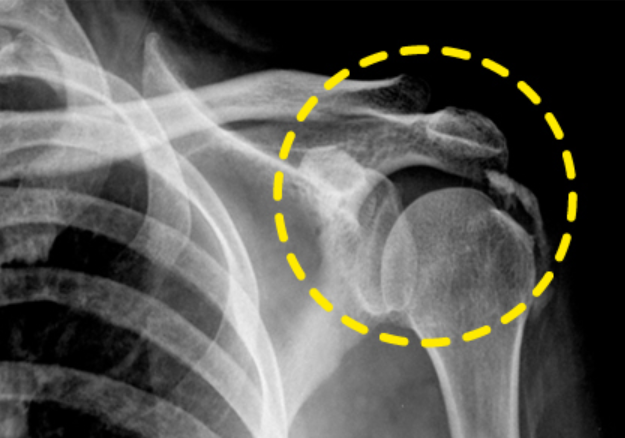

어깨통증 원인 4. 석회성 건염

어깨통증 원인 네 번째는 석회성 건염입니다. 석회성 건염 역시 지속적인 통증보다는 갑작스럽게 어깨 부위에 심한 통증이 느껴질 때 의심할 수 있습니다. 이 때는 밤잠을 이룰 수 없을 정도로 고통을 주는데 보통 노화나 순환 장애로 어깨 부위 특히 힘줄에 칼슘이 축적되며 힘줄과 주변 조직에 통증을 유발하게 됩니다. 질병의 증상은 다양한데 해당 부위를 누르는 경우 심한 통증이 느껴진다면 우선적으로 석회성 건염일 가능성이 높으며 이때도 초음파 촬영이나 X레이 검사를 실시합니다.

석회성 건염 치료는 증상이 심하지 않으면 약물이나 주사치료, 냉·온찜질, 물리치료(체외충격파) 등 비수술적 치료를 우선적으로 실시하며 이러한 방식으로도 통증이 완화되지 않는다면 석회를 제거하는 관절경 수술을 동반합니다. 따라서 여러 이유로 발생하는 어깨통증 원인에 대해 이해를 하시고 가까운 전문병원을 찾아 진단을 받으신 후 증상에 맞는 치료를 받으시기 바랍니다.